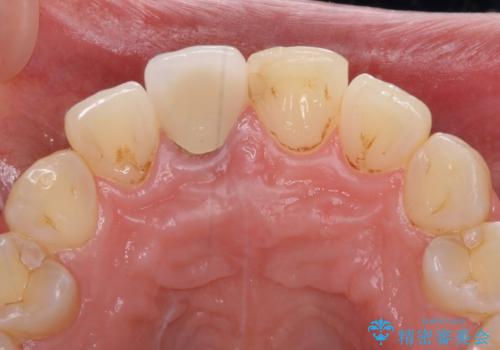

目立つ前歯の詰め物 オーダーメイドのセラミッククラウンで審美的に仕上げる

- 前歯のプラスチックが変色していることを気にして来院された患者様です。

反対側同名歯にセラミッククラウンが装着されていたため、そちらのクラウンと形態や色彩を揃えるようオーダーメイドタイプのオールセラミッククラウンにて補綴することとしました。

2本同時に処置をし、2本とも明るい色合いにすることをお勧めしましたが、今回は1歯のみとしました。

左右のバランスが取れ、患者様には大変満足していただきました。